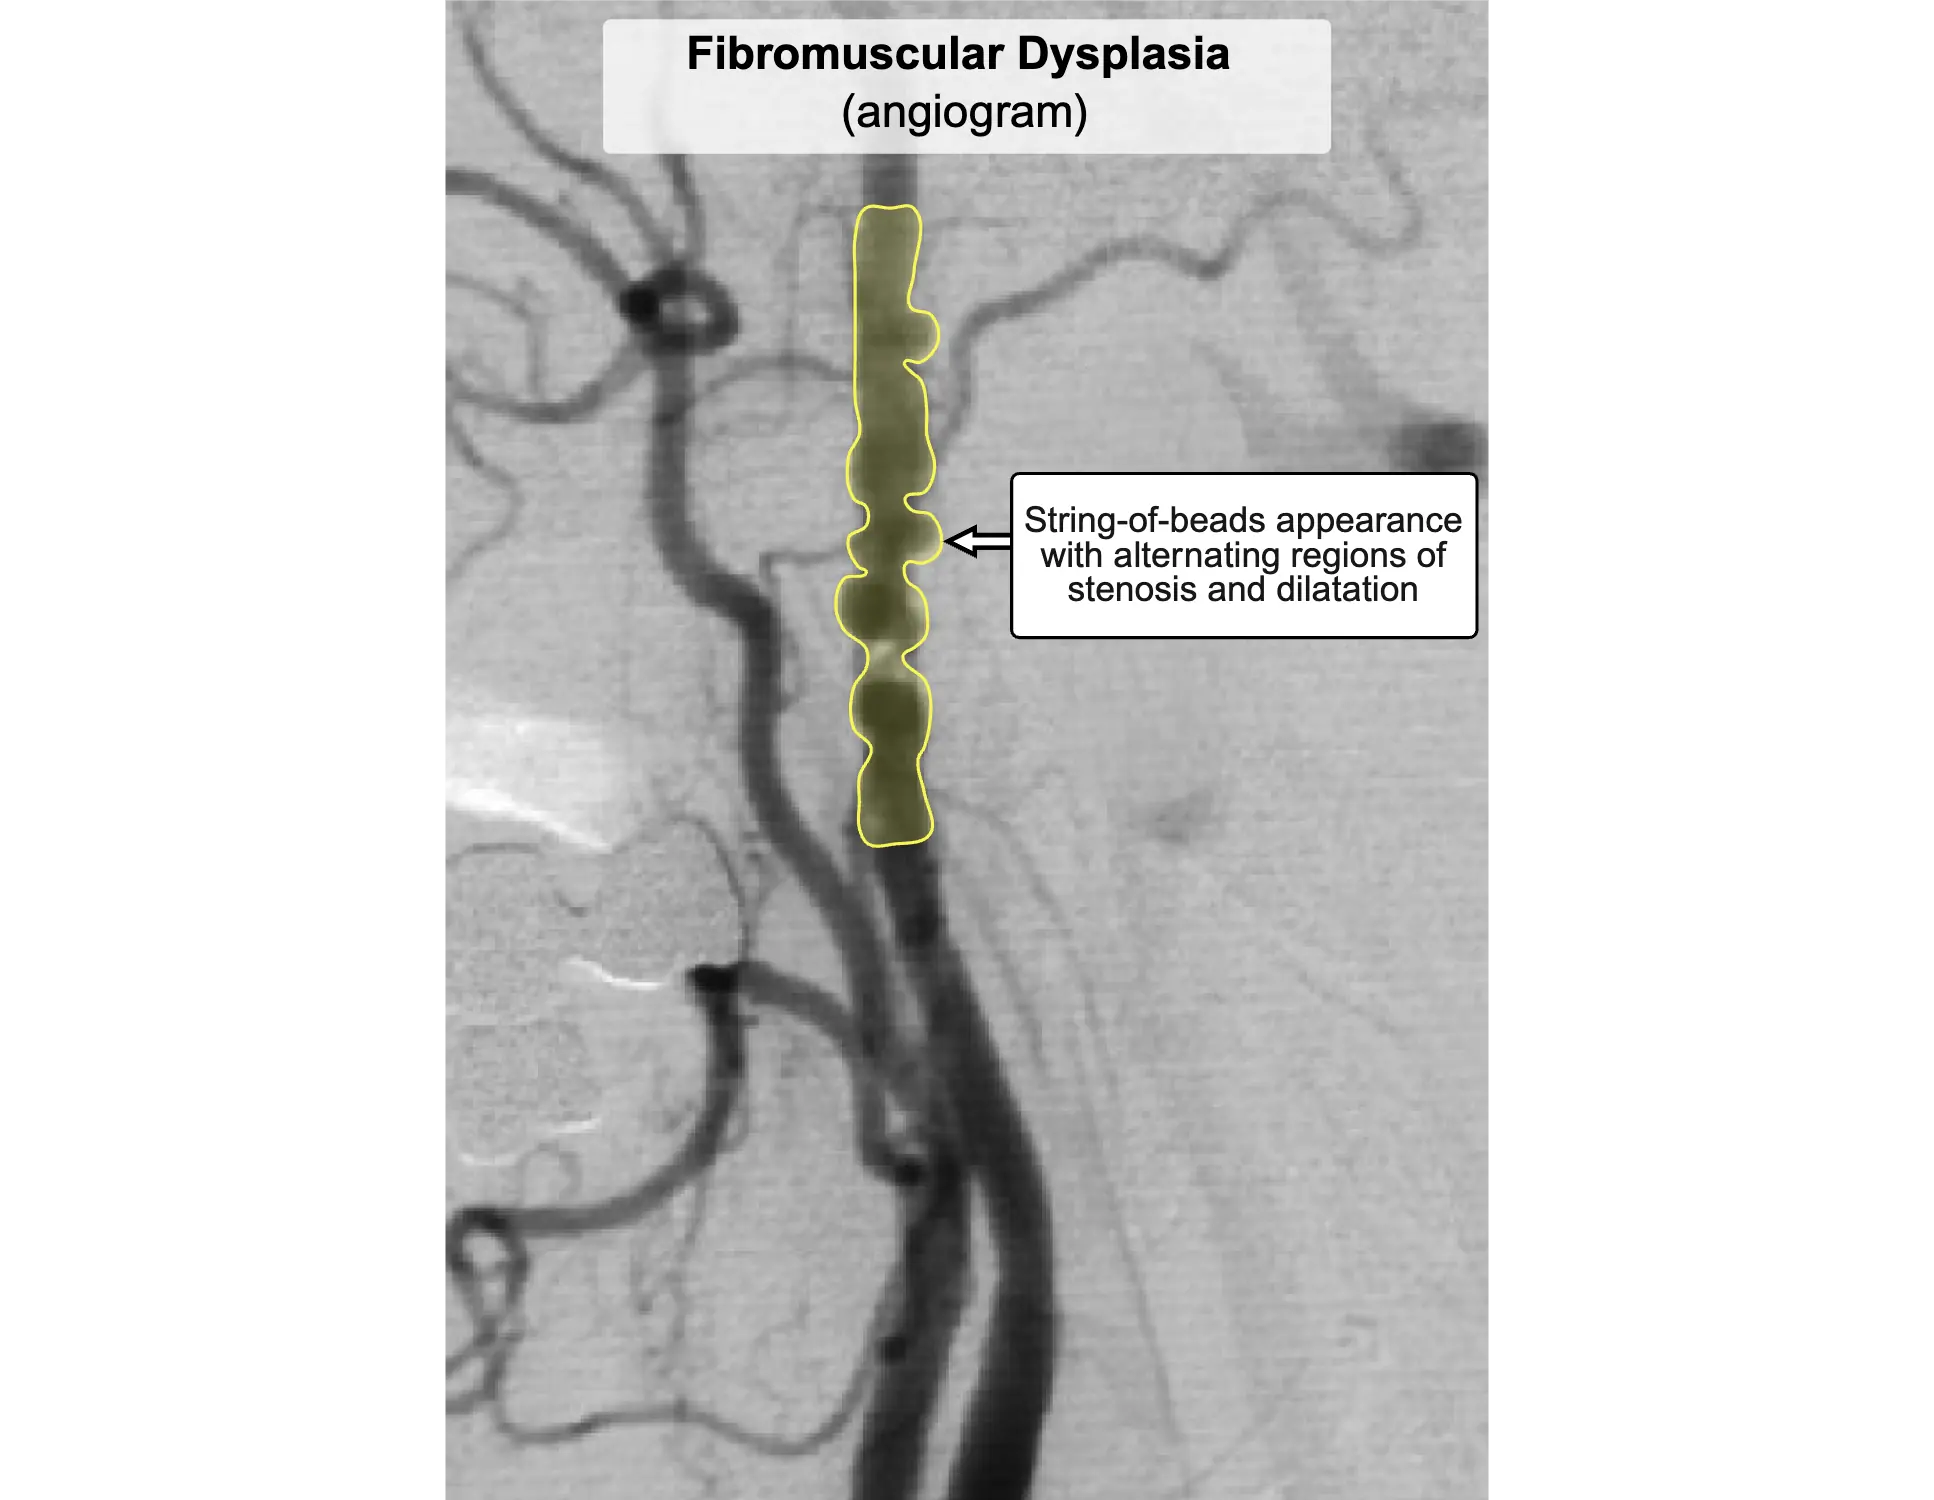

Choice A: Fibromuscular dysplasia is a nonatherosclerotic, noninflammatory vascular disease characterized by abnormal cellular proliferation within arterial walls. It classically presents in young to middle-aged women with resistant hypertension due to renal artery stenosis or headache and tinnitus from carotid artery involvement. This patient's older age, male sex, and classic lower extremity claudication make fibromuscular dysplasia unlikely.